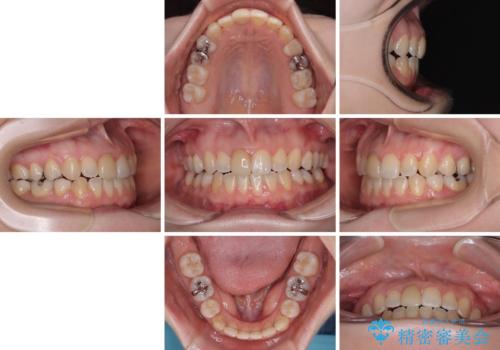

【モニター】後戻りでできた隙間 ワイヤー装置での再矯正

舌の突出癖が非常に強く、その影響で隙間ができてしまったので、舌のトレーニングをしっかりと行っていただきました。

上顎歯列は歯の移動量が少なかったため、セラミッククラウンは装置を装着せずに治療を終えることができました。